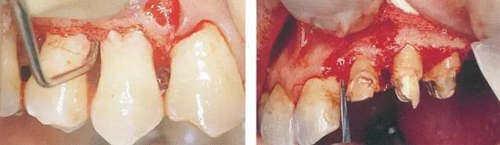

▼圖14-1(左)  用牙齦刀(ARUBA翻瓣器)將牙間部的牙間水平纖維以及牙槽嵴頂纖維切斷。

▼圖14-2(右)  將完全切割分離的組織用牙齦鉗將整塊比較容易的去除。

13.jpg

▼圖14-3  根面和骨面殘存的小肉芽組織,利用刮匙完全去除。炎癥性肉芽組織如果能去除,出血就會變少,清創(chuàng)處理會容易進行。

14.jpg

▼圖14-4  顯示牙冠周圍纖維切斷的圖片。要點是利用手術(shù)刀片或牙齦刀(aruba翻瓣器)將根面與骨面結(jié)合的纖維群徹底的切斷。

15.jpg